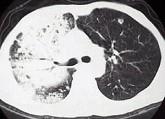

问题 男,30岁,咳嗽咯血,盗汗1个月,伴消瘦无力发热,CT如图,应考虑为 ( )

选项 A.右上肺大叶性肺炎 B.右上肺干酪性肺炎 C.右侧脓胸 D.右上肺多发肺脓肿 E.右上肺不张

答案 B